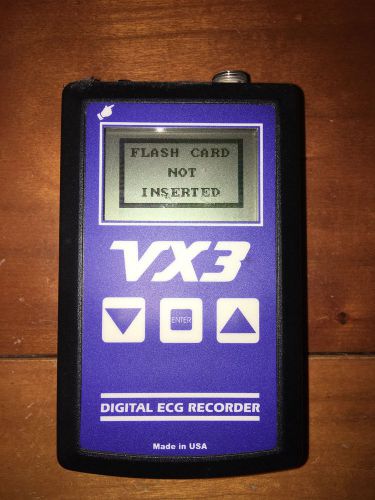

Datrix VX3i Series A Holter Recorder